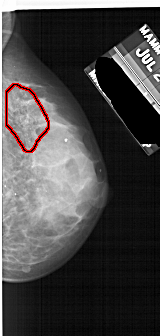

A_1734_1.LEFT_MLO

LEFT_MLO LINES 5176 PIXELS_PER_LINE 2326 BITS_PER_PIXEL 12 RESOLUTION 43.5 NON_OVERLAY

FILE: A_1734_1.RIGHT_MLO.OVERLAY

TOTAL_ABNORMALITIES 1

ABNORMALITY 1

LESION_TYPE CALCIFICATION TYPE PLEOMORPHIC DISTRIBUTION SEGMENTAL

ASSESSMENT 4

SUBTLETY 3

PATHOLOGY BENIGN

TOTAL_OUTLINES 1

BOUNDARY